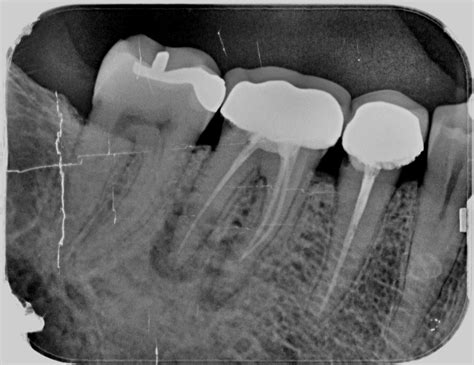

El objetivo del tratamiento endodóntico es eliminar la infección que ha afectado al nervio y conservar el diente sin dolor. Si esto no se logra en un tiempo razonable, estamos ante un tratamiento fallido. Además, es posible que los síntomas se manifiesten incluso años después del tratamiento. Un diagnóstico claro solo puede establecerlo tu dentista mediante exámenes complementarios como radiografías, pruebas de sensibilidad y estudios clínicos.

- Sellado corto de los conductos: En caso de que el dentista realice un sellado corto o incompleto de las raíces, existen altas posibilidades de que el tratamiento fracase. Ya que, posteriormente, las bacterias podrán entrar desde el final de la raíz y esto ocasiona nuevamente una infección.

- Perforación radicular: Esto puede surgir mientras se hace la endodoncia y se endurece la búsqueda de conductos radiculares. Generalmente, el especialista utiliza un material denominado MTA, para sellar la grieta provocada. En la mayoría de casos la evolución suele ser favorable, aunque se recomienda vigilar en los meses siguientes la endodoncia.

- Tratamiento de reendodoncia: En algunos casos, se puede intentar hacer un retratamiento del conducto radicular para corregir cualquier problema del tratamiento inicial e intentar salvar el diente. Es un procedimiento más complejo que la endodoncia inicial, ya que pueden quedar restos de material, haber conductos obstruidos o lesiones periapicales.

- Cirugía periapical: Si no es posible realizar el retratamiento o no funciona, la cirugía periapical es la única alternativa para evitar extraer el diente. Suele ser la solución más eficaz cuando hay una lesión localizada, el diente tiene una restauración que no se puede retirar sin dañarlo o cuando el canal está bloqueado.